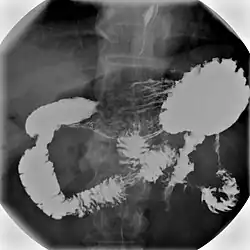

- Barium swallow X-ray examinations are used to study the pharynx[4] and esophagus.[2]

- Barium meal examinations are used to study the lower esophagus, stomach and duodenum.[2]